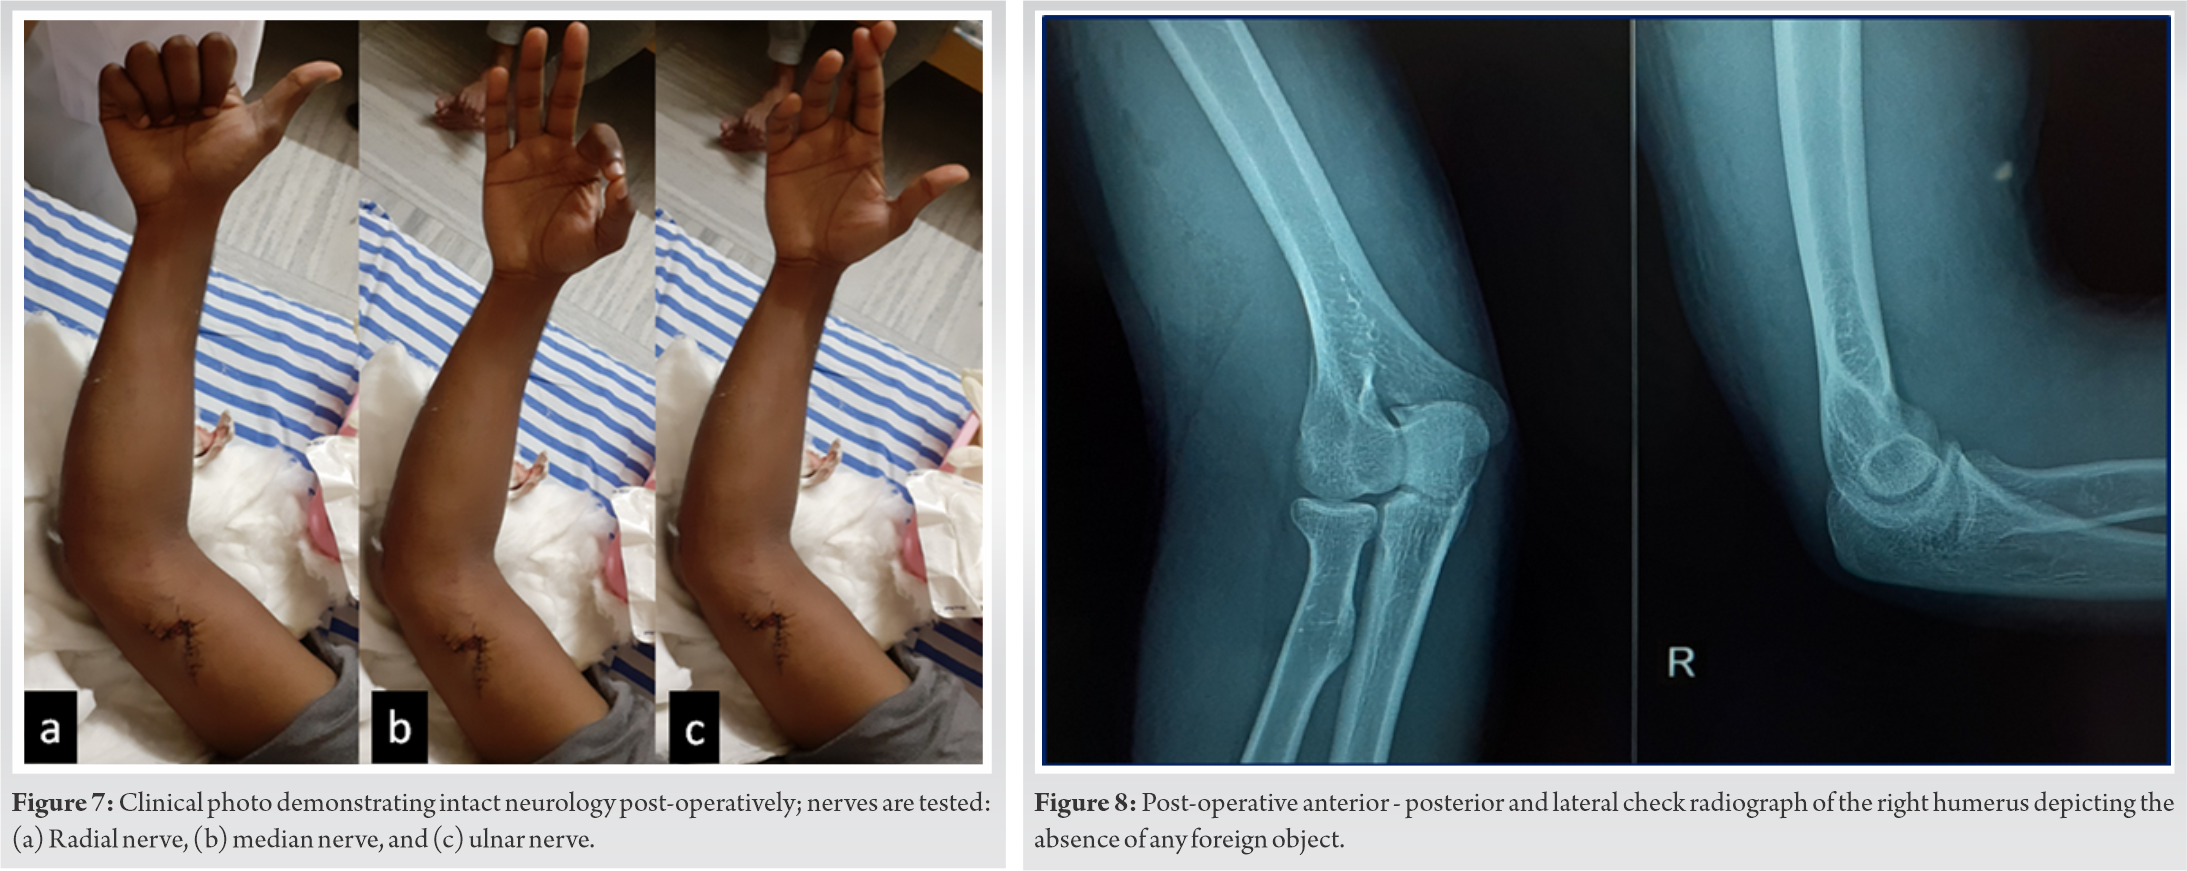

Postoperatively, neurology was assessed and was normal (Fig. 7). A check radiograph was taken for documenting the absence of any foreign objects (Fig. 8).